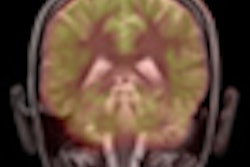

So-called "mad cow disease" and other variants of Creutzfeldt-Jakob disease (CJD) can be particularly difficult to diagnose, but advances in MRI are helping to make the task easier. In some cases, the modality can lead to a correct diagnosis, even when the clinical information, electroencephalography, and cerebrospinal fluid analysis data are uncertain.